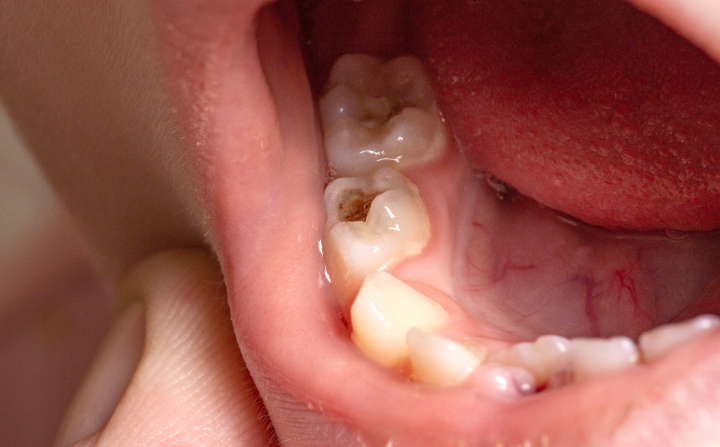

子どもは、大人に比べて虫歯になりやすいといわれています。乳歯や生えたばかりの永久歯は、一度虫歯になると進行するのが早いため重症化しやすいという特徴があります。

特に虫歯ができやすい場所としては、上顎の前歯と前歯の間や奥歯同士の間、奥歯の溝、歯と歯ぐきの境目などが挙げられます。また、乳歯にできる虫歯は黒ではなく、白いことが多いのも特徴のひとつです。

そのため、虫歯ができていても気付かずに放置するケースが少なくありません。

子どもの歯は石灰化が進んでいないため歯質が弱く、柔らかいという特徴があります。また、歯の表面のエナメル質も薄いため、虫歯ができやすいだけでなく進行が早いです。